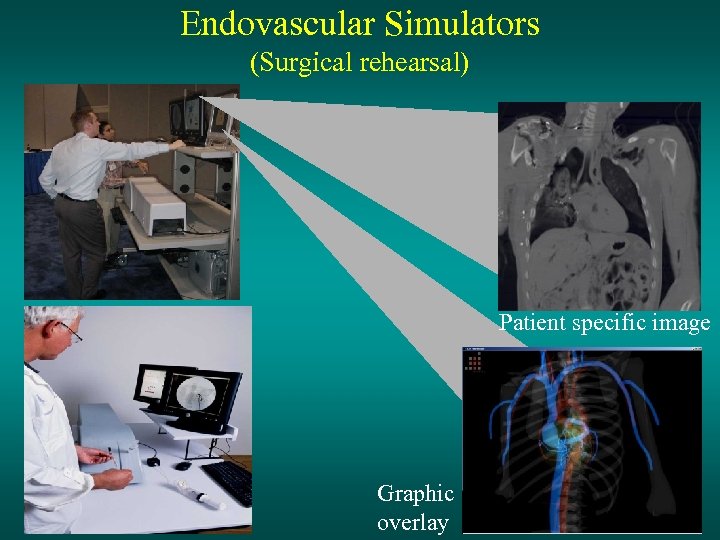

Endovascular Simulators (Surgical rehearsal) Patient specific image Graphic overlay

Endovascular Simulators (Surgical rehearsal) Patient specific image Graphic overlay